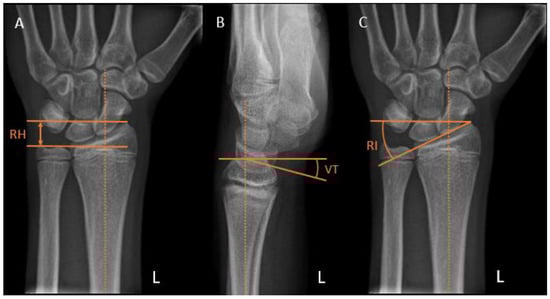

Radial height is measured on posteroanterior (PA) views as the distance between two parallel lines: one perpendicular to the long axis of the radius along the ulnar aspect of the articular surface and the other one at the tip of the radial styloid (Figure 3A). A normal adult radial height is 8 to 14 mm [13]; however, the values range in the literature, and those for children are unknown.

Volar tilt is measured on the lateral view as the angle between a line drawn perpendicular to the long axis of the radius and a tangent line along the slope of the articular surface of the radius (Figure 3B). A normal volar tilt ranges between 10 and 25 degrees [14,15].

Radial inclination is measured on the PA view as the angle between a line perpendicular to the long axis of the radius at the level of the radial styloid tip and a line along the articular surface of the distal radius (Figure 3C). A normal radial inclination ranges between 15 and 25 degrees [14,16].

Figure 3. Distal radius radiographic reference lines. (A) Radial height (RH). (B) Volar tilt (VT). (C) Radial inclination (RI).